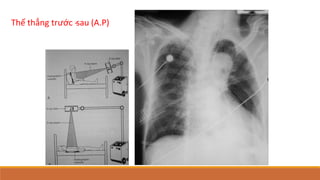

Thế thẳng trước ‐sau (A.P)

Thế